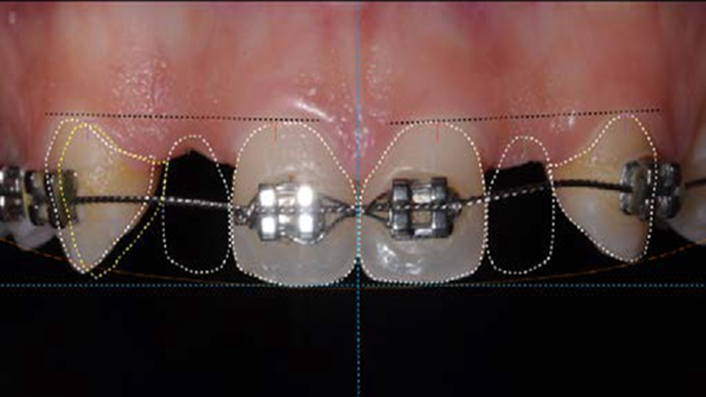

Clinical case: Immediate placement in maxillary anterior narrow space using Advanced Intermezzo

- Courtesy of Dr. Jung Sam Lee, Korea -

Keywords

Advanced Intermezzo. anterior esthetics, esthetic, provisional restoration, esthetic zone, #13, maxillary anterior, Dr. Jung Sam Lee, anterior aesthetics, aesthetic, aesthetics

Products:

Advanced Intermezzo implant system